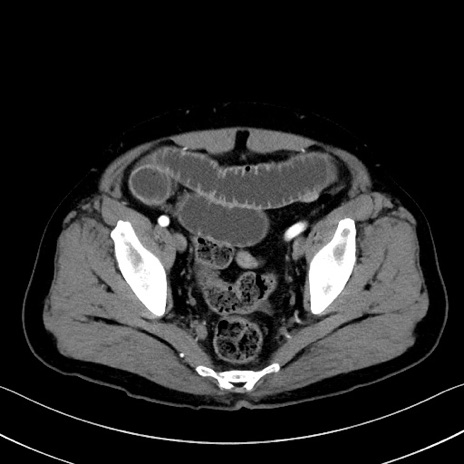

冠状断像

【症例】70歳代 男性

【主訴】腹部膨満、嘔吐

【現病歴】昨日より腹部膨満感出現。本日増悪し、仙痛出現。嘔吐あり、受診。

【既往歴】糖尿病、胆摘後

【身体所見】BP 149/80mmHg、HR 74/min、BT 35.9℃、腹部:膨満、軟、圧痛なし。腸雑音減弱あり。上腹部正中切開瘢痕あり。

【データ】WBC 13500、CRP 1.72